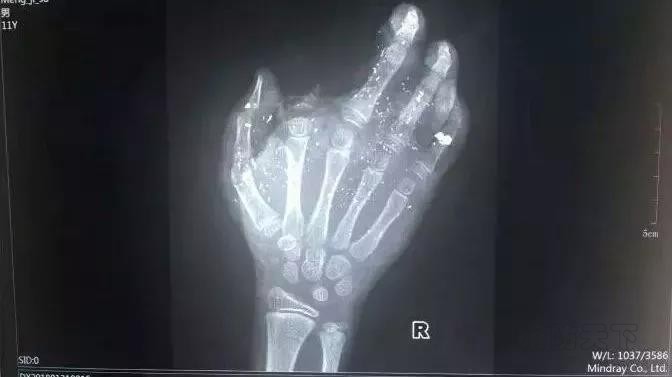

2018年1月31日上午,廣西發生一起手機爆炸事件,一名年僅12歲的小男孩手掌被炸得血肉模糊,其中一個斷指無法再接!